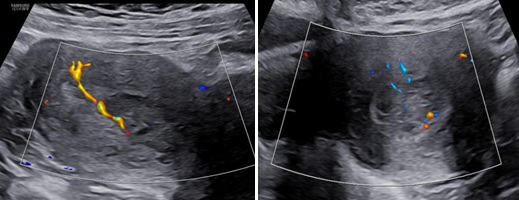

Hình 2: Trên Doppler màu, khối trong lòng tử cung tăng sinh mạch máu mức độ 2

Hình 3: (trái: ngã âm đạo, phải: ngã bụng): Trên Dopple màu, phần tổn thương ở cổ tăng sinh mạch máu độ 4, không ranh giới giữa tổn thương và cơ vùng cổ tử cung